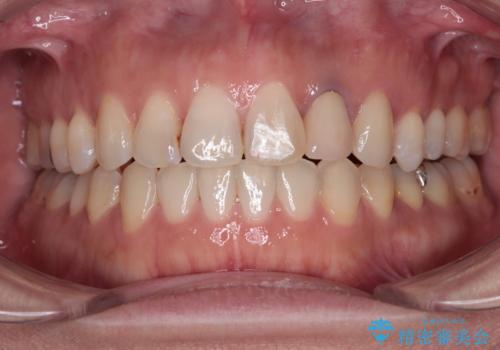

- 右上の小臼歯部に咬んだときに強い痛みを感じるとのことで来院された患者様です。

診査を行った結果、根管治療を行った後にオールセラミッククラウンにて補綴する治療計画となりました。